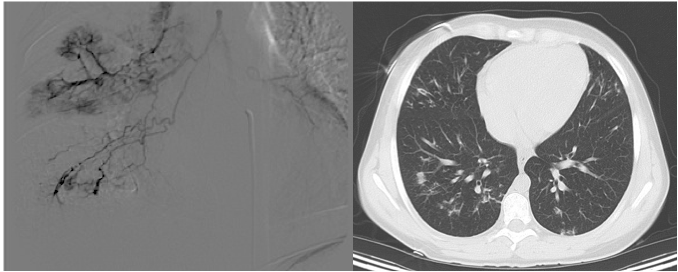

History

A Caucasian child had Cystic Fibrosis (CF) diagnosed at birth with a positive sweat chloride test, and required surgery as a neonate for meconium ileus. A liver biopsy at three months of age demonstrated focal biliary cirrhosis, and the patient suffered from esophageal varices that required sclerotherapy until eighteen months of age. From the age of two onwards the patient did not have further clinical manifestations of cirrhosis. Her pulmonary symptoms were not significant, and imaging demonstrated mild bronchiectasis of the right middle and lower lobes. Genotyping was done during adolescence, and she was found to have one copy of ΔF508 while the second mutation remained unknown.